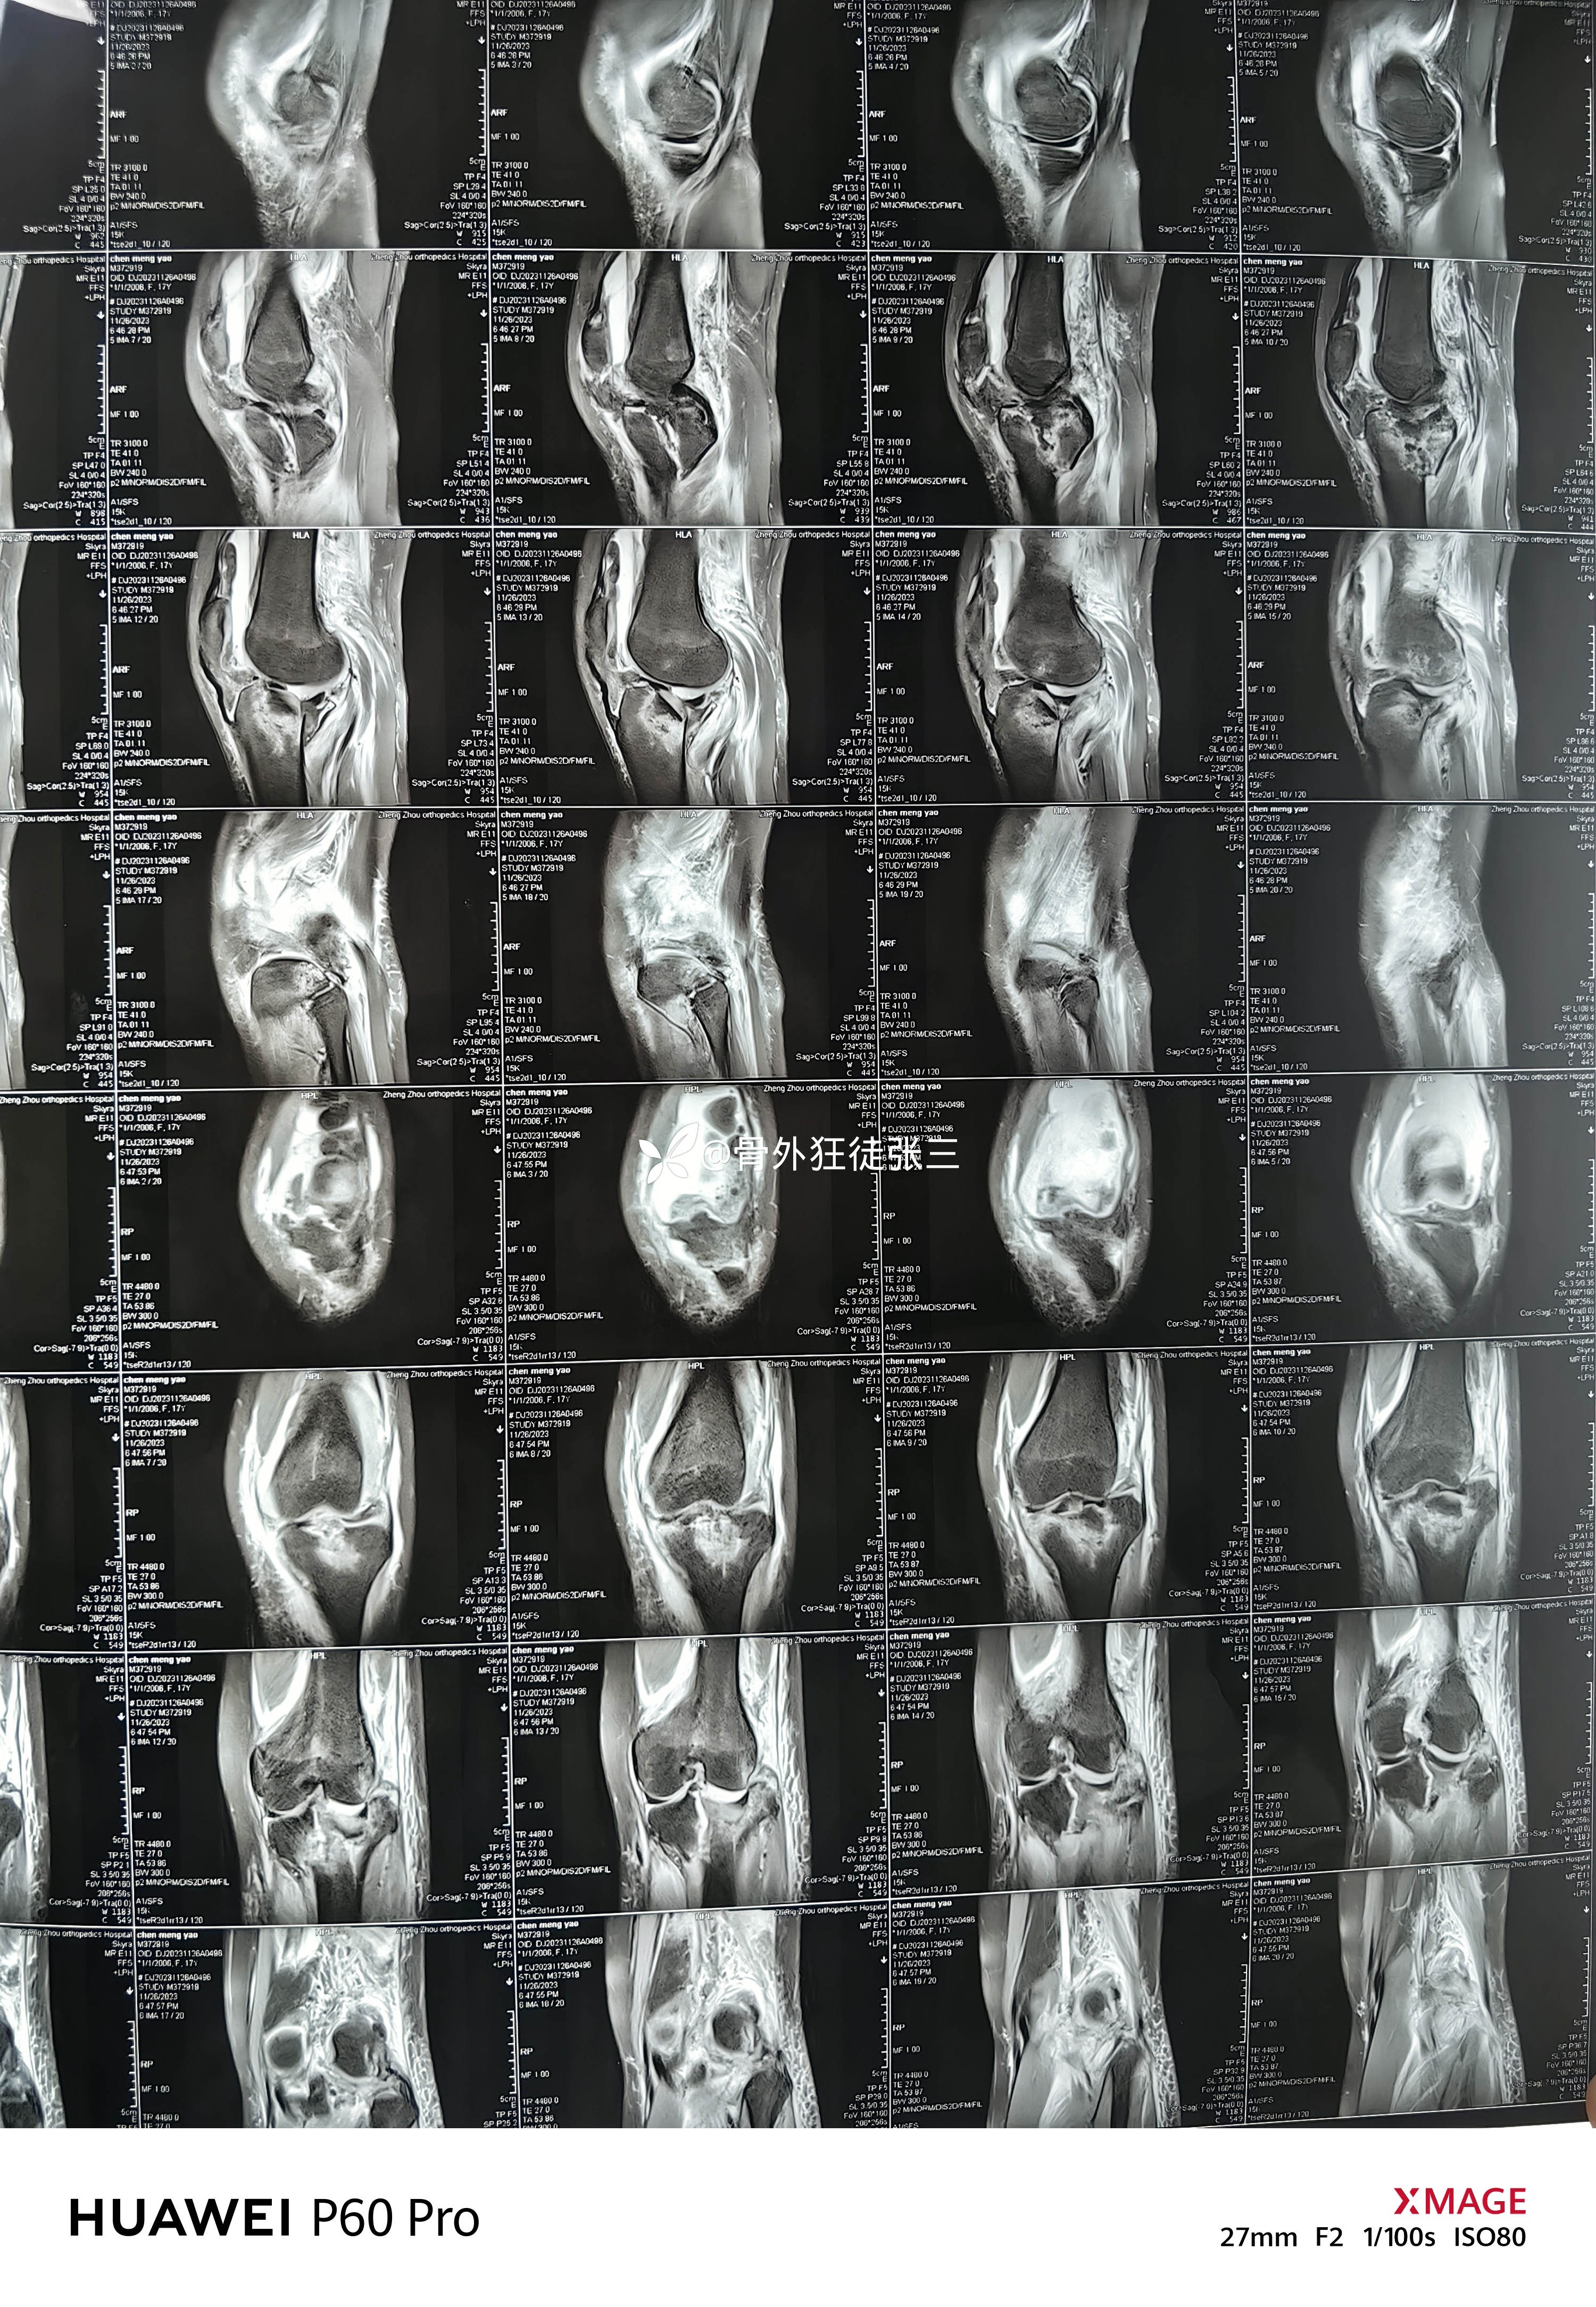

辅助检查:

第一次手术后复查

第二次手术后复查

在我院复查